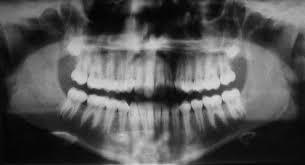

Primera radiografía dental en los Estados Unidos (en cráneo).Por William J. Morton.

Otto Walkhoff tomó la primera radiografía dental en sus propios maxilares.